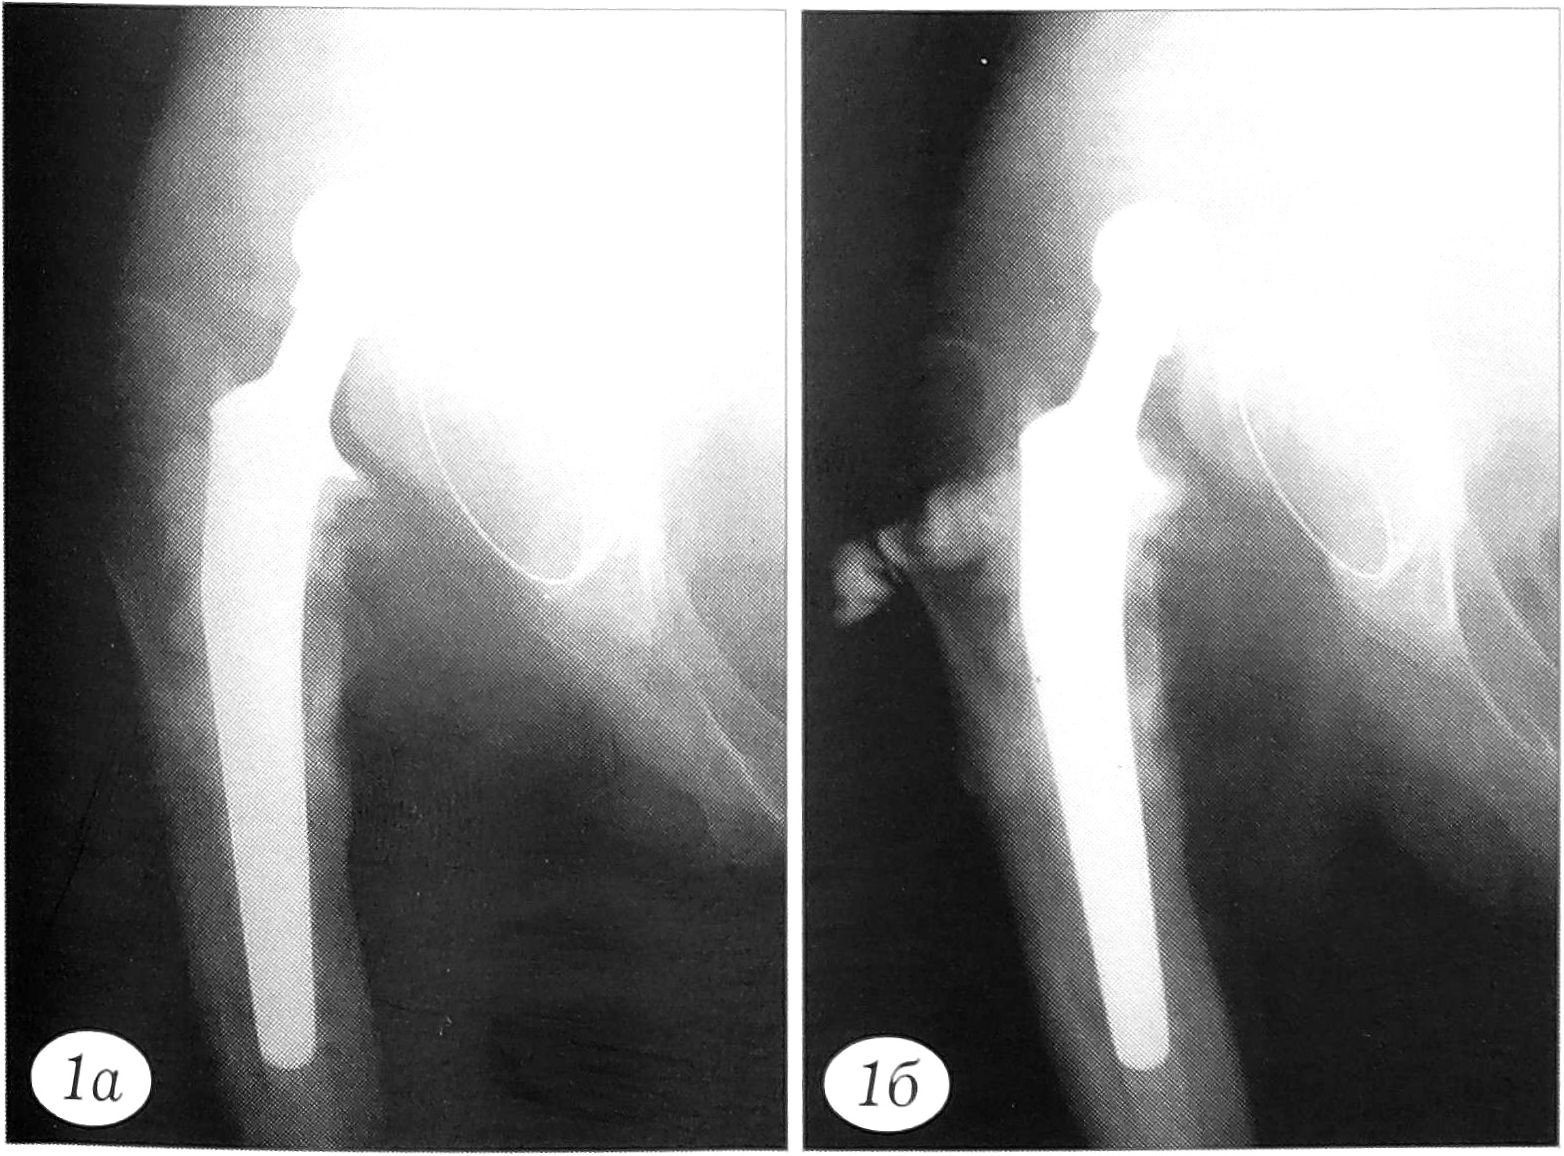

Всем больным при поступлении проводили рентгенографию тазобедренного сустава. При наличии свищей дополняли ее фистулографией с тугим заполнением свищевого хода контрастным веществом, что позволяло выявить нестабильность металлофиксатора или эндопротеза, расположение очагов резорбции вокруг их элементов, распространенность процесса в костной и окружающих мягких тканях, а также нарушение целости имплантата (рис. 1-3).

Рис. 1. Рентгенограмма (а) и фистулограмма (б) больного X. 39 лет при поступлении. Ранее по поводу хронического гематогенного остеомиелита головки правой бедренной кости были выполнены резекционная секвестрнекрэктомия проксимального отдела бедра и первичное эндопротезирование тазобедренного сустава протезом «Protek» с использованием костного цемента. Через 1 мес в связи с нестабильностью вертлужного компонента произведена его замена. Через 6 мес в области послеоперационного рубца открылся свищ. Диагностирован хронический остеомиелит проксимального отдела бедренной кости с вывихиванием эндопротеза. Поступил через 1 год после эндопротезирования и 5 мес после развития гнойно-воспалительного процесса.

Рис. 2. Рентгенограмма (а) и фистулограмма (б) больного У. 36 лет при поступлении. Ранее по поводу перелома шейки левой бедренной кости был выполнен остеосинтез трехлопастным гвоздем с пластиной Лена. Через 10 дней после операции развился гнойно-воспалительный процесс. Через 1 мес выявлены нестабильность конструкции, остеомиелит проксимального отдела бедренной кости. Поступил через 3 мес после остеосинтеза.